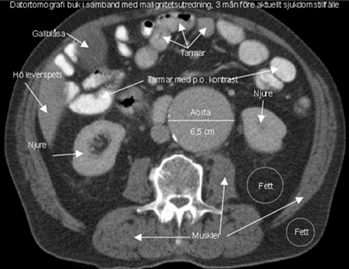

Vad ser du på denna bild?

Vad ser du på bilden?